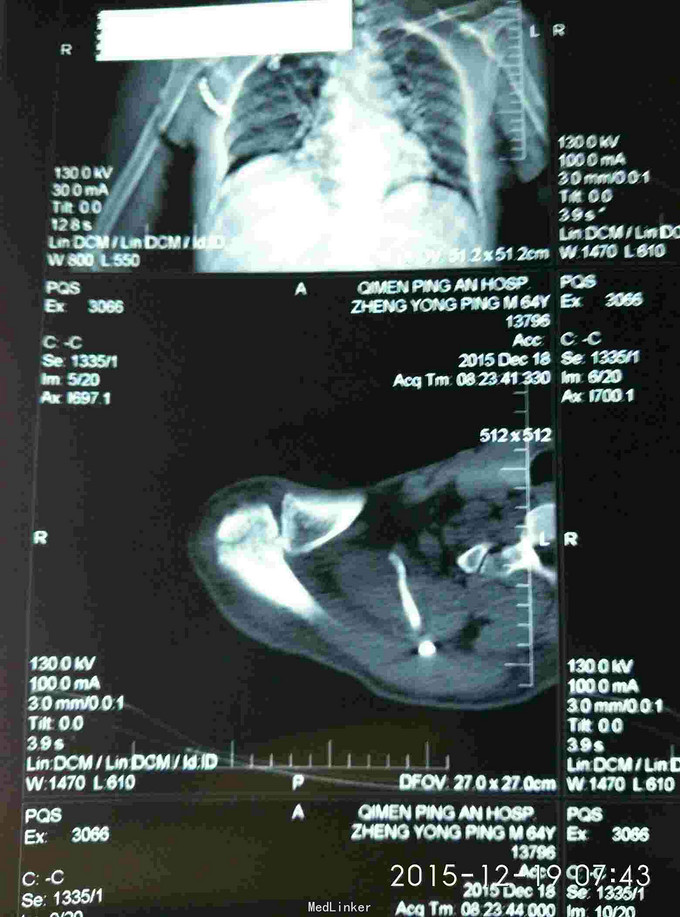

右肩峰及肩胛骨骨折

骨折 肩峰骨折 肩胛骨骨折

胸廓挤压试验阳性,右肩峰压痛阳性,右肩主动活动受限,外展约30度。x片及CT示右肩峰骨折及肩胛骨骨折,右第6.7.8.9肋骨骨折。

右肩峰骨折,右肩胛骨骨折,右第6.7.8.9肋骨骨折